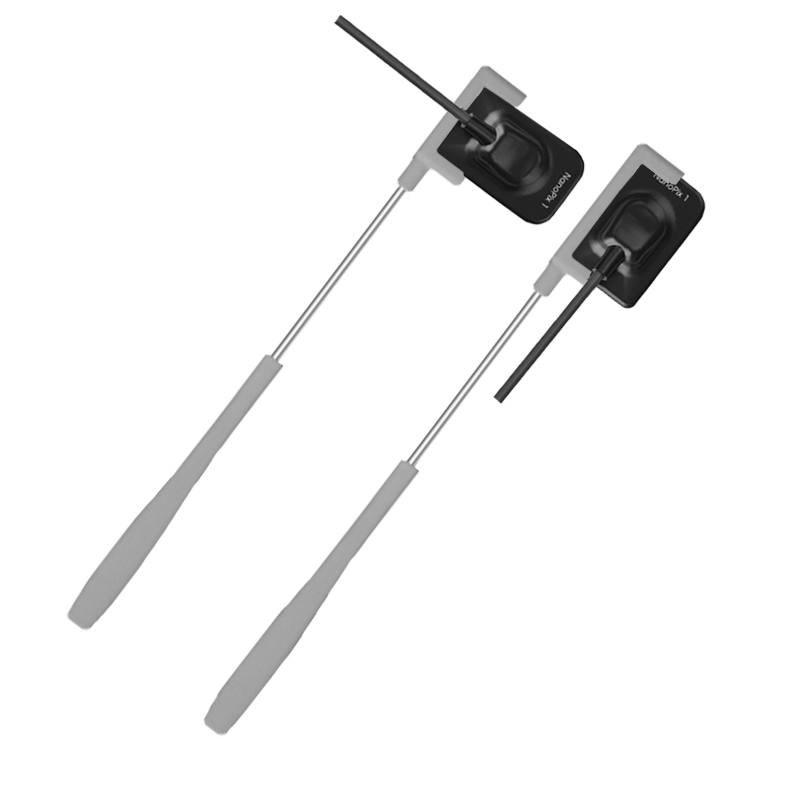

Визиограф NANOPIX с искусственным интеллектом (Nano AI)

Описание:

Прибор оснащён высокочувствительным сенсором, с помощью которого устройство фиксирует и передаёт изображение в цифровом виде на компьютер. Принцип работы заключается в следующем: цифровой радиовизиограф размещается в ротовой полости пациента за зубами. С щёчной стороны дентальный рентгеновский аппарат выпускает в направлении радиовизиографа рентгеновские лучи. Лучи, проходя через ткани зуба, фиксируются на радиовизиографе, и полученная информация отображается на экране компьютера. Уникальная технология искусственного интеллекта Nano AI распознаёт зубные патологии, выделяя их цветом и предлагая возможные способы лечения.

- Эргономичный дизайн;

- Супертонкий рентгеновский датчик - 4.4 мм;

- Округлая форма без острых углов для максимального уровня комфорта пациента;